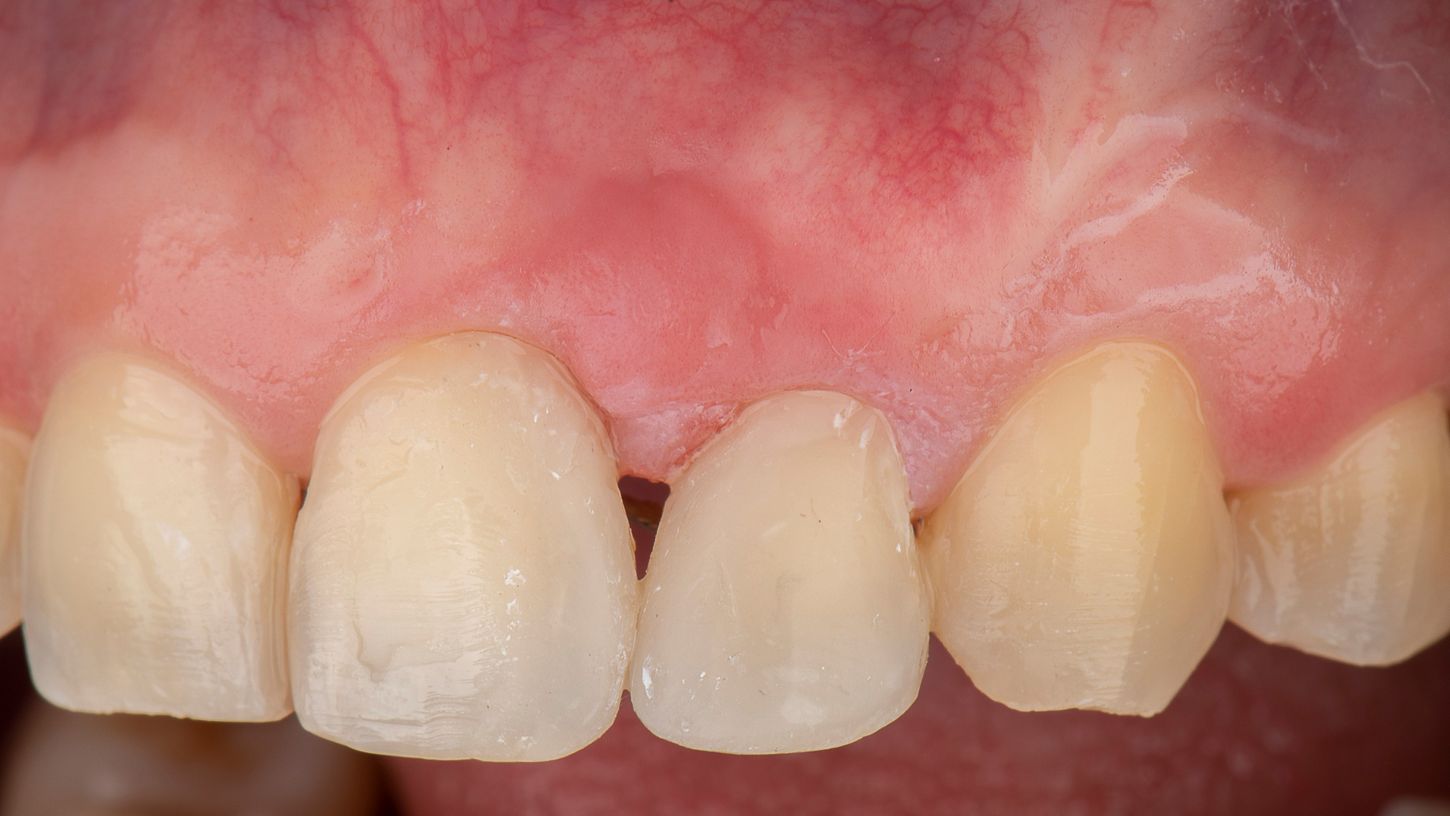

A 46-year-old male healthy (ASA I), non-smoker, with no medication, was referred to our practice for a papilla reconstruction in the anterior esthetic zone. The intraoral examination revealed a protruded and extruded tooth #22, localized erythema and edema at teeth #21 and #22, with a severe loss of the interproximal papilla. The periodontal examination revealed a PPD of 8 mm at teeth #21 and #22, and established a diagnosis of localized stage III, grade C periodontitis (Fig. 1). The radiographic examination revealed a severe vertical osseous defect (Fig. 2).

Clinical outcomes exceeded patients’ expectations and were very satisfactory for the ortho-perio team. The soft tissues remain stable after 5 years of interdisciplinary treatment (Fig. 16). The patient expressed deep gratitude for saving his teeth: “Thanks to the entire team for collaborating so diligently over these years; the wait was truly worthwhile.”